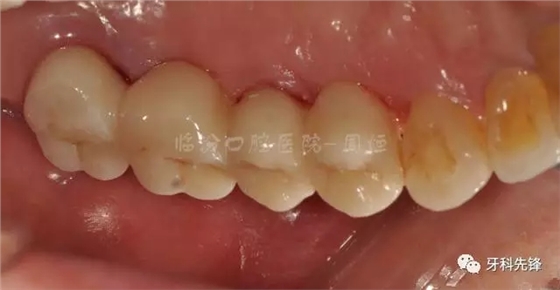

圖30術(shù)后頜面照

640.webp (34).jpg